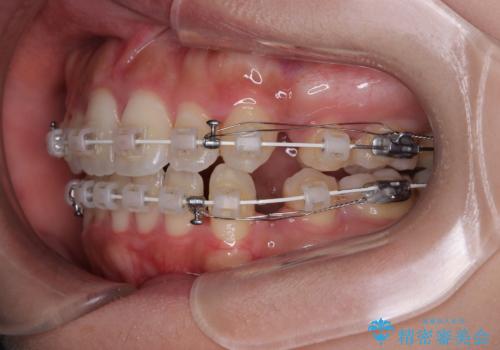

- 審美装置

- 1年10ヶ月

- 口元の突出感と口の閉じにくさを気にして来院された患者様です。

上下左右第一小臼歯4本を抜歯し、ワイヤー装置にて口元を引っ込めるよう矯正治療を行うこととしました。

口元の突出感が改善されてことで、下唇に引っかかっていた上顎前歯も気にならなくなりました。